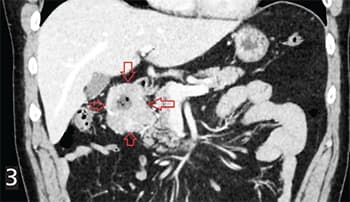

Рисунок 3. Экзоорганная форма. ГИСО 12-перстной кишки с инвазией в головку поджелудочной железы, мета- стазами в регионарных лимфоузлах, микрометастазами в большой сальник.При экзоорганной форме роста опухоль исходит из стенки органа ЖКТ, но растет в брюшную полость (см. рис. 3).